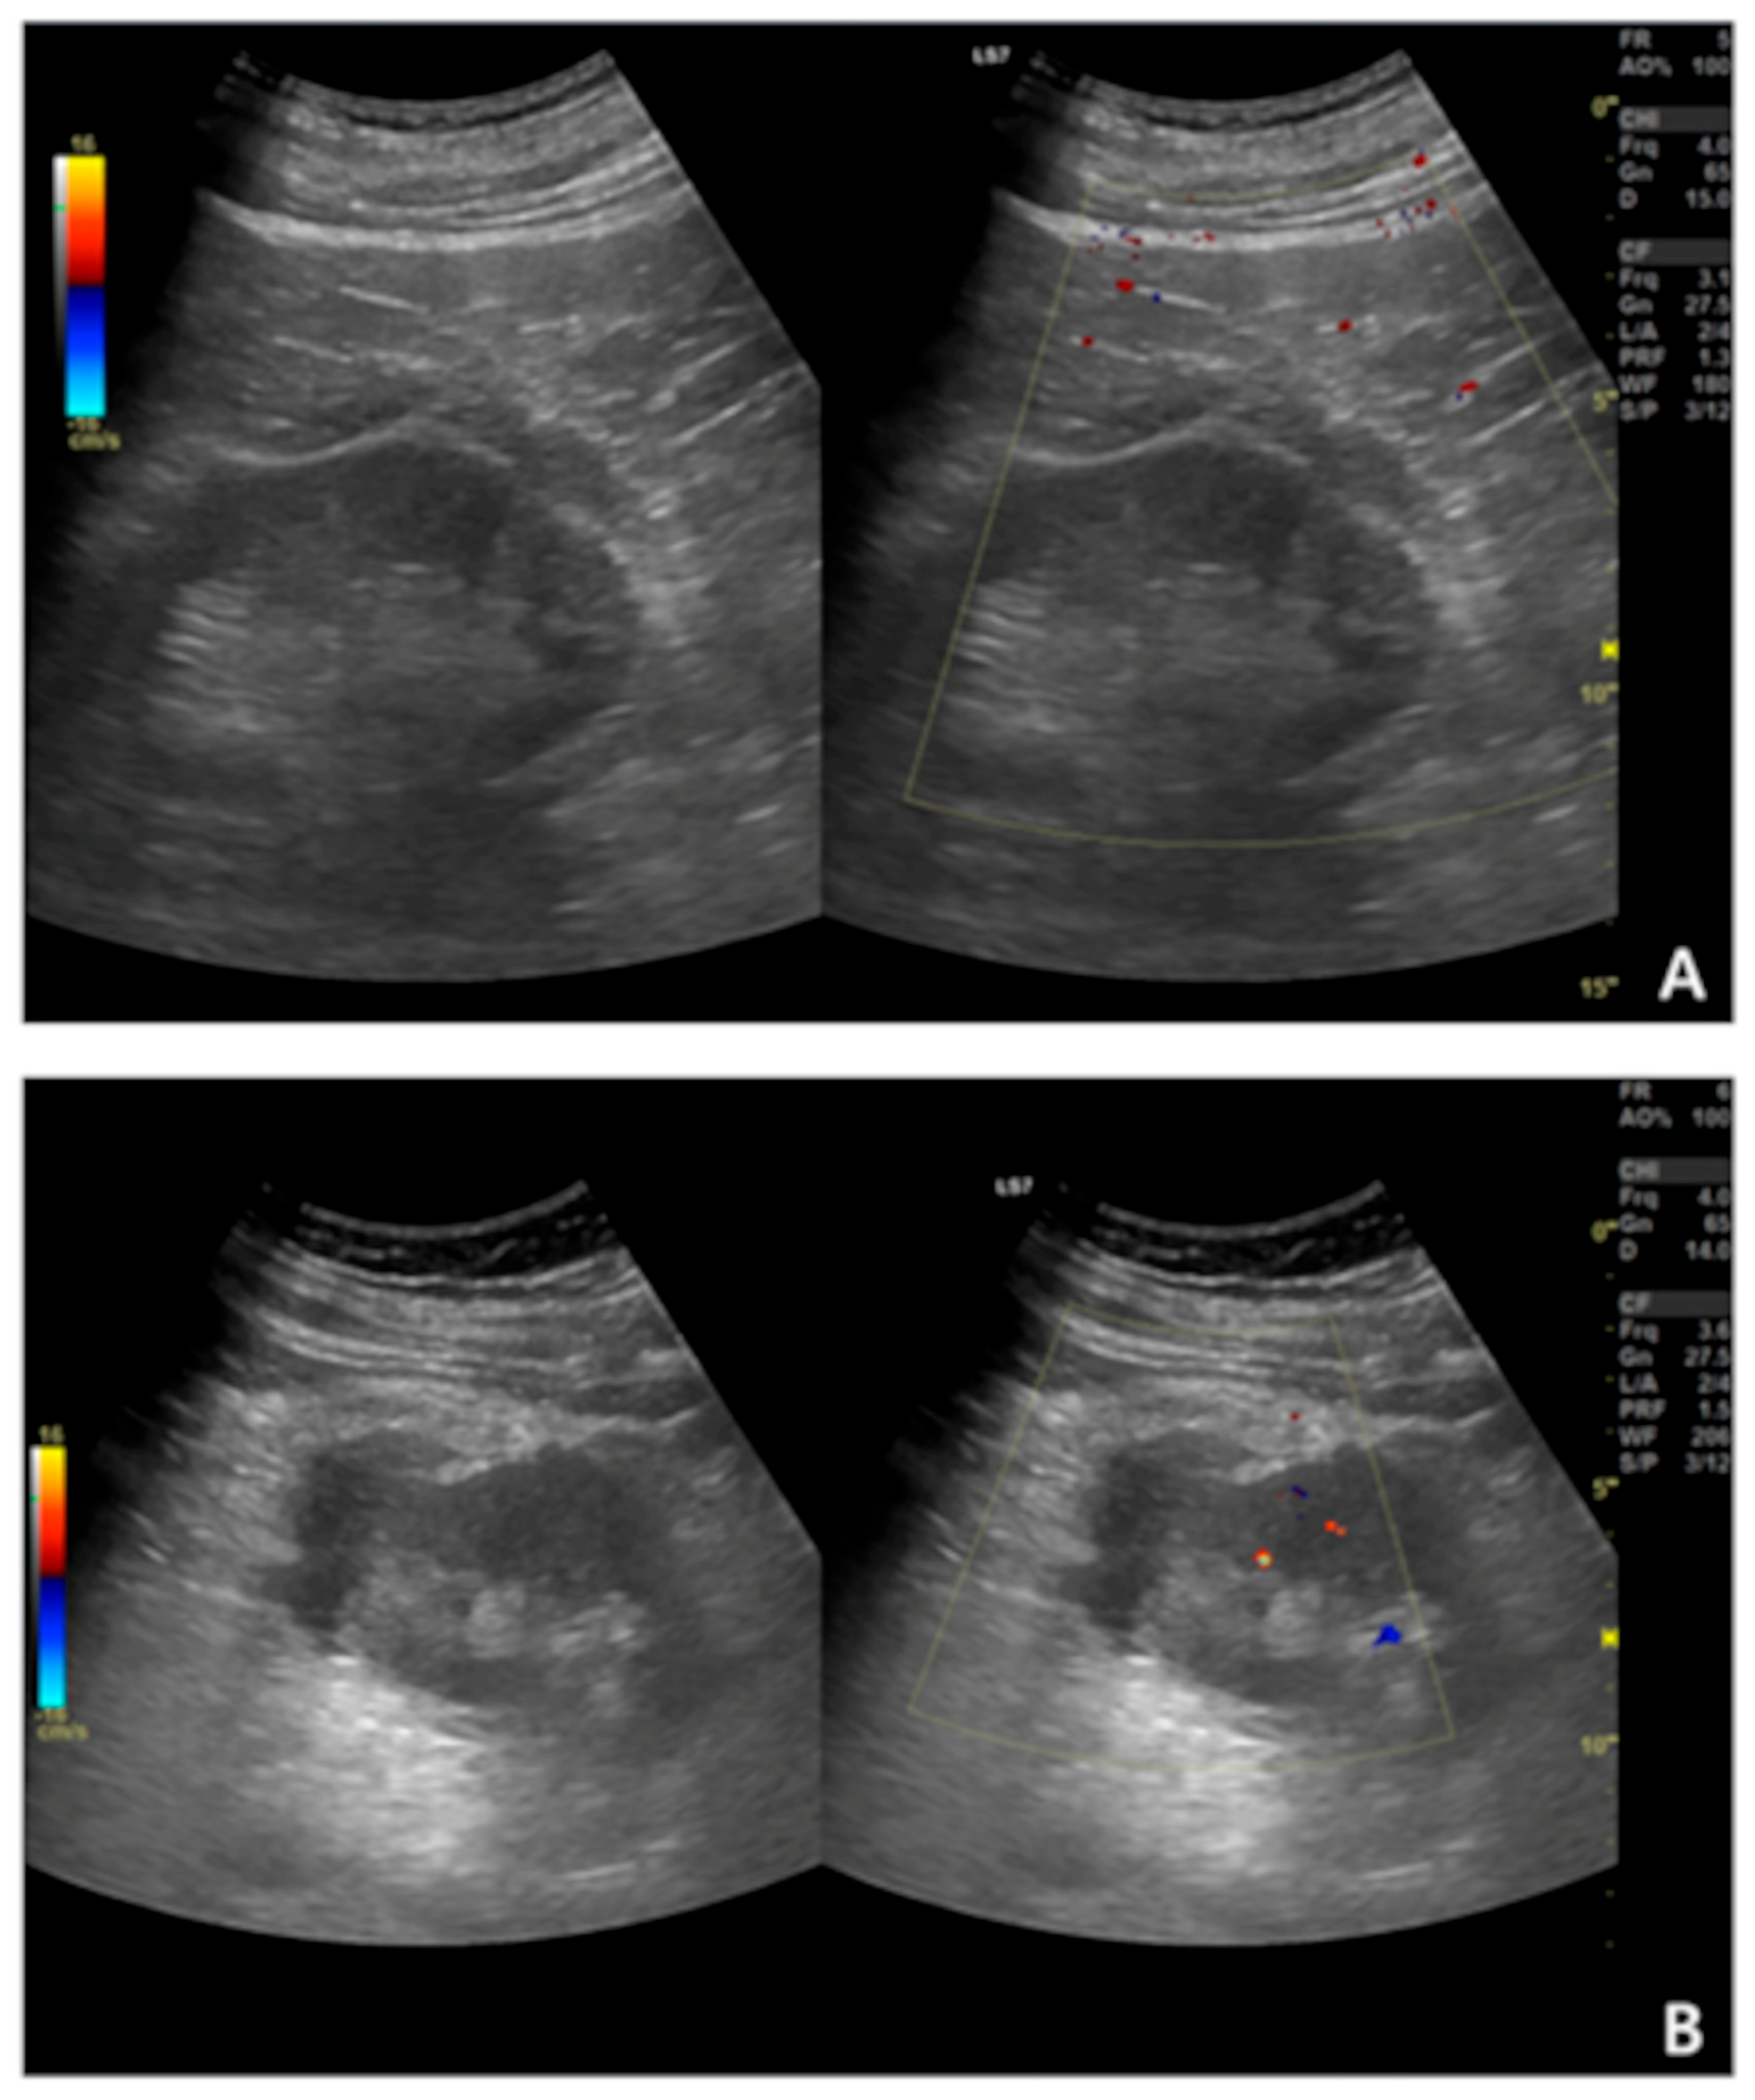

- Granata, A.; Campo, I.; Lentini, P.; Pesce, F.; Gesualdo, L.; Basile, A.; Cantisani, V.; Zeiler, M.; Bertolotto, M. Role of contrast-enhanced ultrasound (Ceus) in native kidney pathology: Limits and fields of action. Diagnostics 2021, 11, 1058. [Google Scholar] [CrossRef]